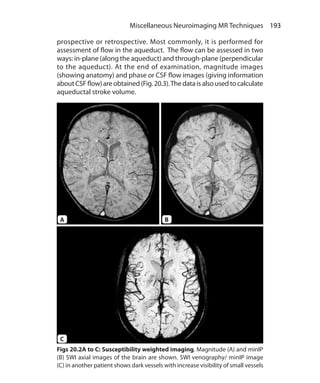

V

Valvular heart disease 177

Vascular access ports 89

Venous infarct 105f

Vertical long-axis plane 174

Volume